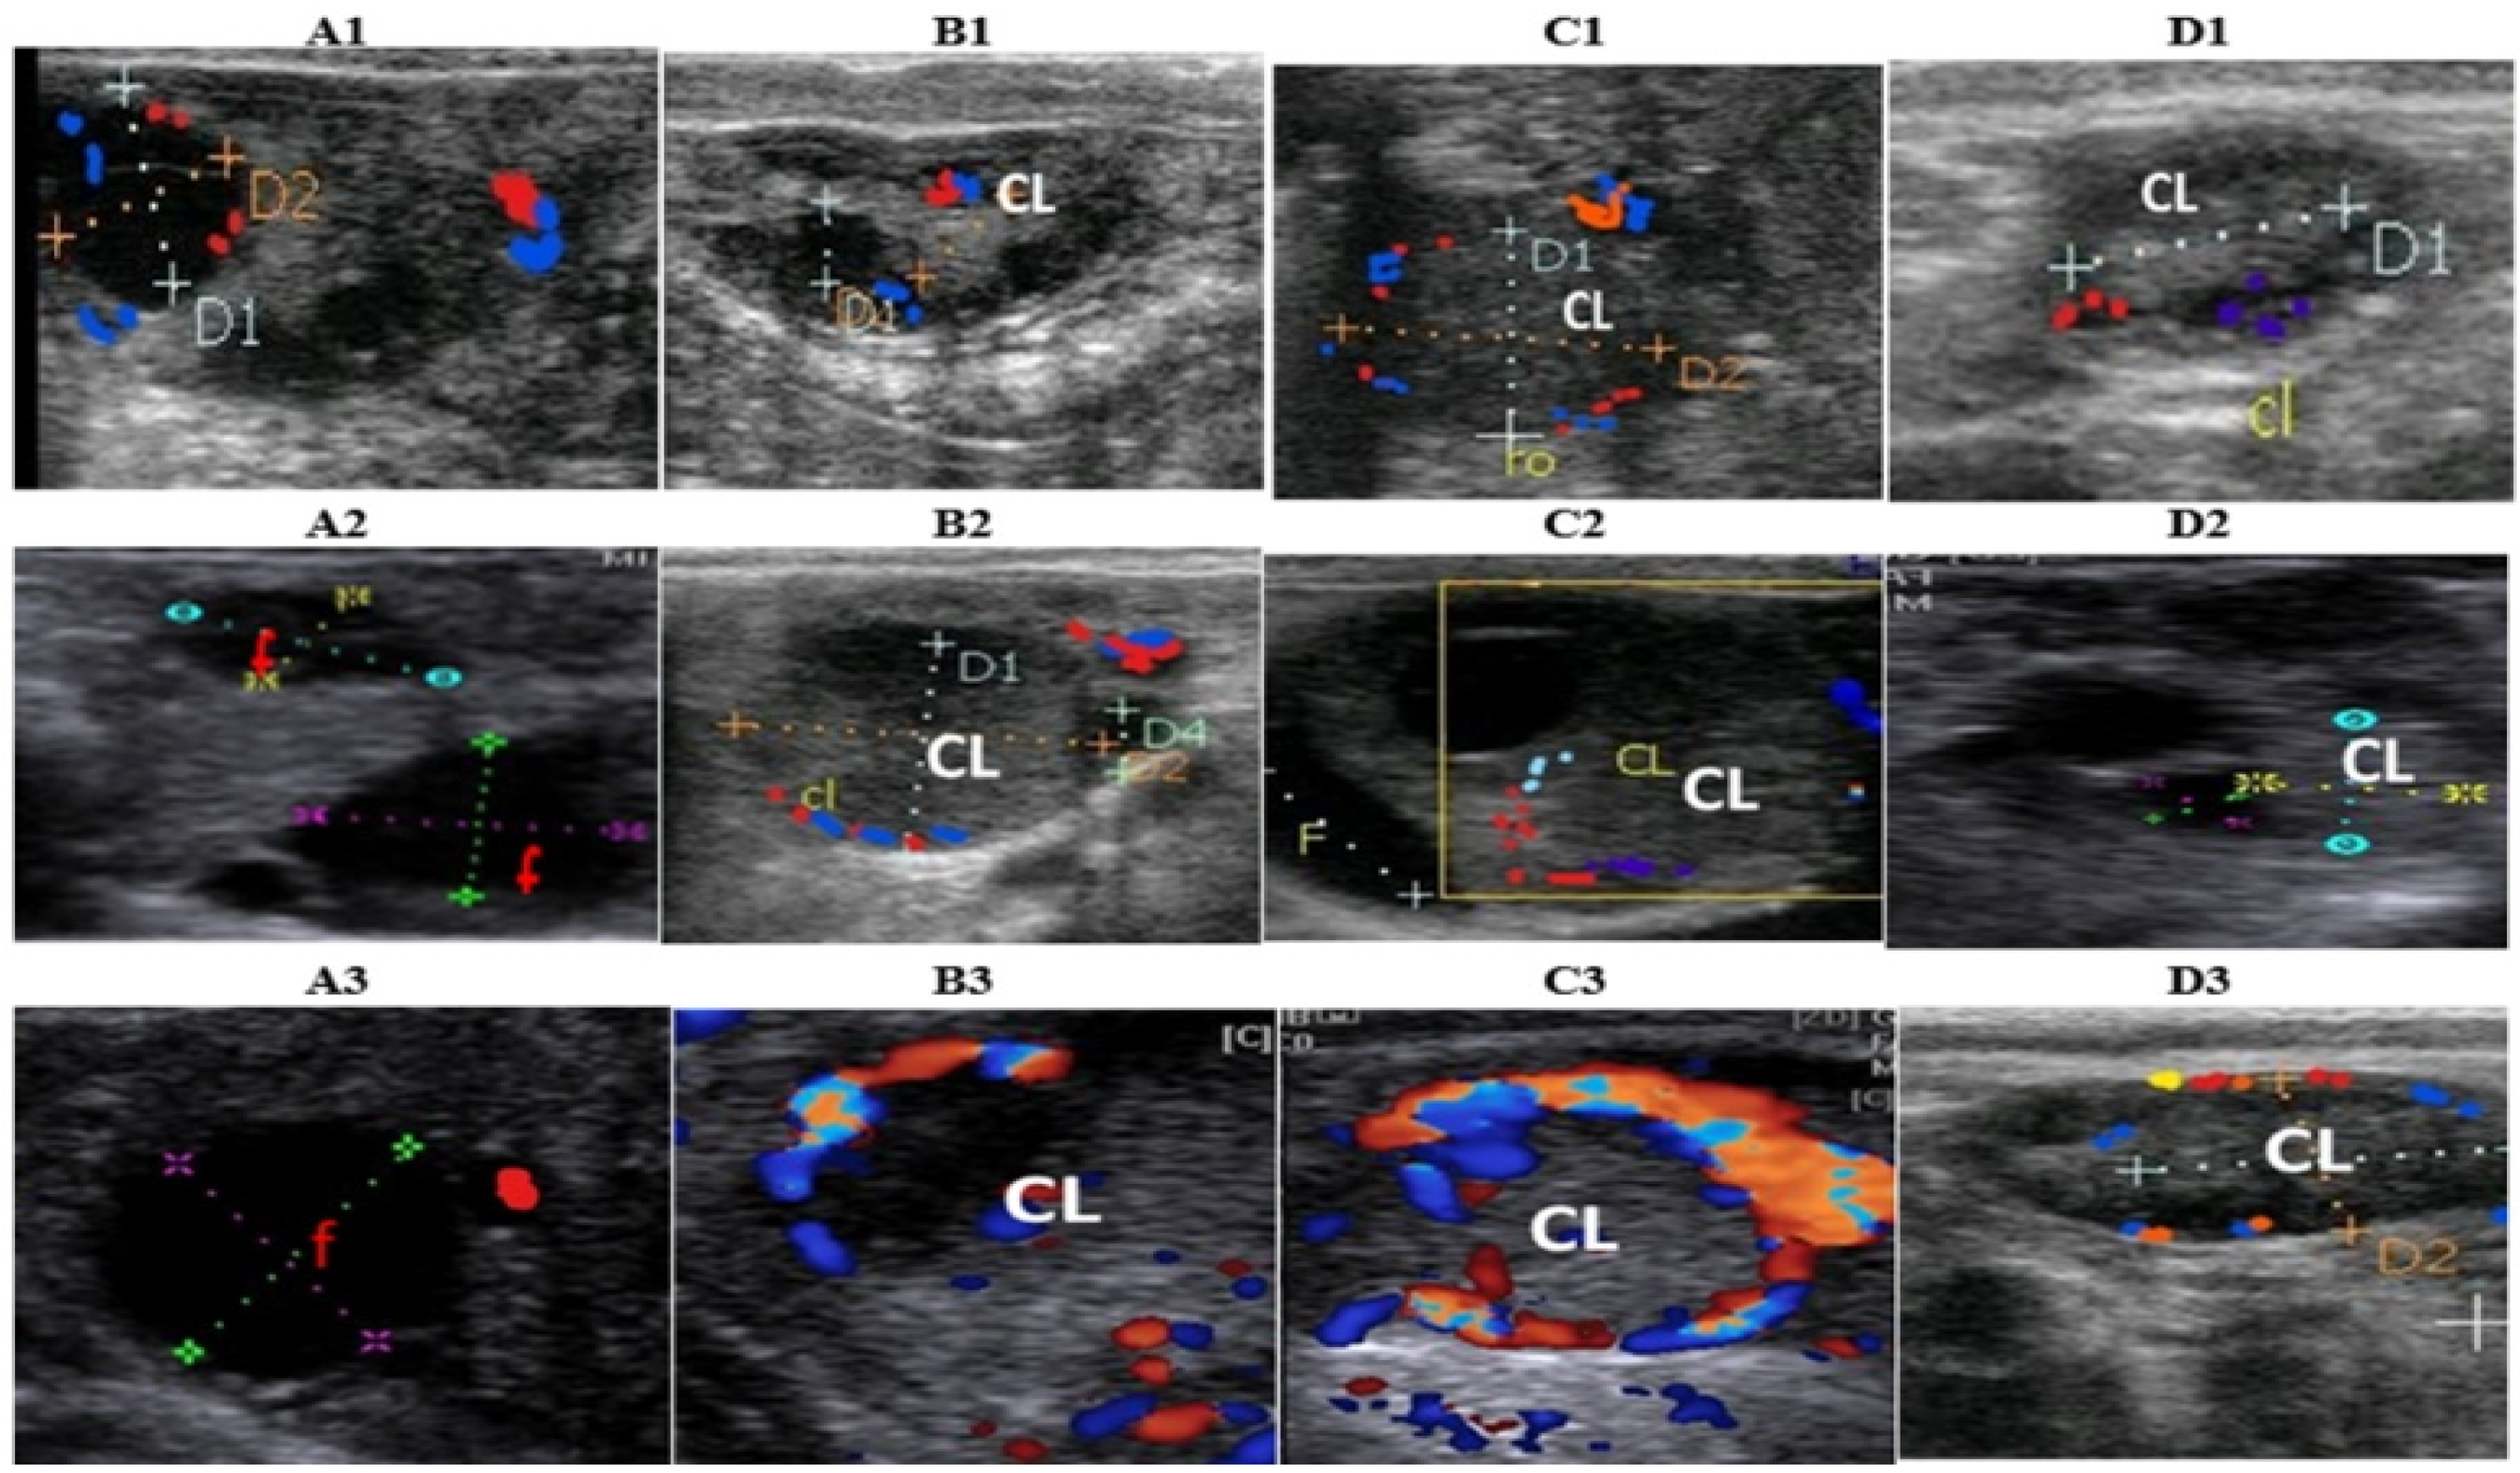

2.3. Ultrasonography Evaluation of Ovarian Structures and Hemodynamic Pattern

3.2. Effect of Common or Nanodelivered Ovsynch Protocols on Ovarian Structures

3.3. Effect of Common or Nanodelivered Ovsynch Protocols on Hemodynamic Indices